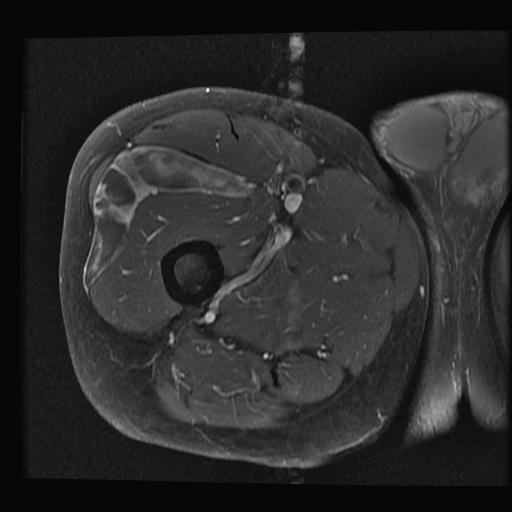

Cuboid Fractures

2. Body / Nutcracker fracture

Nutcracker fracture

Mechanism

- forced eversion / abduction of forefoot

- cuboid crushed between 4th and 5th MT and calaneum

Pathology

- displaced cuboid fracture with subluxation of tarsus